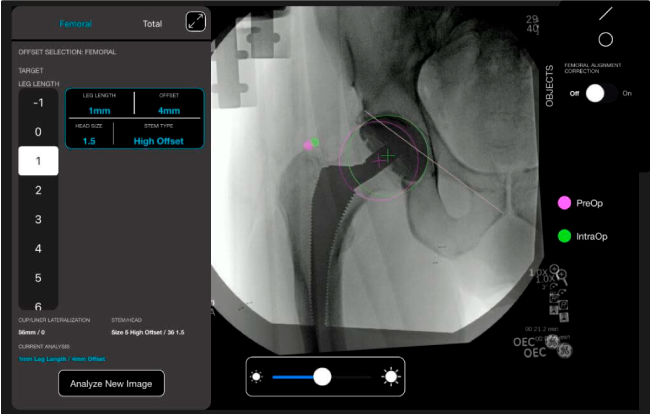

Desplazamiento y offset para posicionamiento óptimo del componente (vástago) femoral.

Anotaciones digitales y herramientas de análisis de longitud de pierna.

Con tecnología ONETRIAL® que calcula automáticamente el cambio en la longitud de la pierna y el desplazamiento para todas las combinaciones de implantes en una tabla fácil de leer.

Favorece la restauración biomecánica del offset femoral.

Mayor nivel de información intraoperatoria facilita la colocación correcta de los implantes: